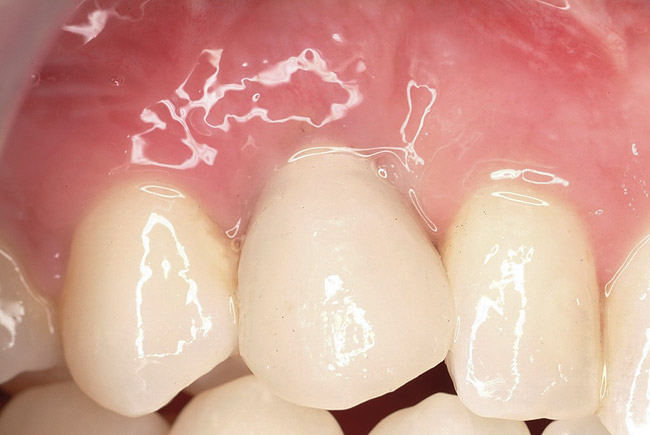

A 26-year-old woman presented with a history of trauma combined with an impacted maxillary right canine (No. 6), which was extracted in early childhood. Following two courses of orthodontic therapy—one in her early teens and the second in early adulthood—the area had reportedly been grafted approximately 9 months prior to her initial presentation to the author’s private periodontal practice. Clinically, the edentulous site appeared healthy, with significant keratinized mucosa in the canine position (Figure 1). A cone-beam CT scan revealed severe horizontal bone deficiency in the proposed implant position (Figure 2). Adequate bone height for implant placement was evident; however, the thinnest portion of the ridge measured approximately 0.45 mm in width. It was proposed that an augmentation be performed to facilitate implant placement, which the patient accepted.

Figure 1  In Case 1, the patient’s edentulous site appeared healthy, with significant keratinized mucosa in the canine position.

Figure 1